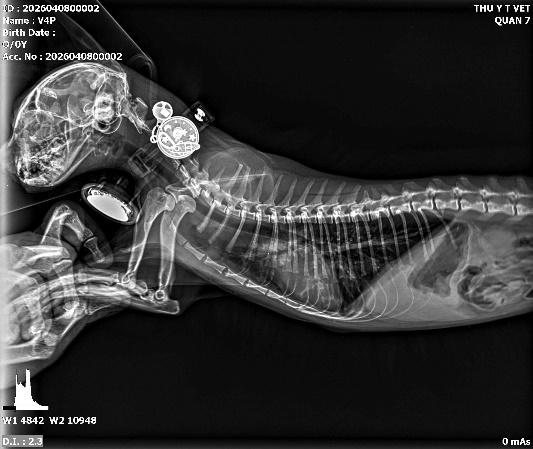

Phổi là cơ quan cực kỳ nhạy cảm. Khi mèo hoặc chó của bạn có dấu hiệu khó thở, khò khè hoặc ho kéo dài, việc nghe tim phổi bằng ống nghe đôi khi không đủ để đưa ra kết luận chính xác.

Thông qua phim chụp X-quang ngực, chúng tôi có thể quan sát được độ tương phản của nhu mô phổi. Những hình ảnh như:

• Phế quản viêm: Đường dẫn khí dày lên tạo thành hình "đường ray" hoặc "bánh vòng".

Hình ảnh: viêm phế quản, viêm phế nang

• Phù phổi/Viêm phổi: Các đám mờ (thâm nhiễm) xuất hiện thay vì màu đen của không khí.

• Tràn dịch màng phổi: Chất lỏng lấp đầy khoang ngực, ép xẹp nhu mô phổi, khiến con vật khó thở cấp tính.

Hình ảnh: phổi thủng khí tràn ra ngoài mô

Việc phát hiện sớm giúp chúng ta đưa ra phác đồ kháng sinh hoặc thuốc giãn phế quản chính xác, tránh tình trạng suy hô hấp dẫn đến tử vong.